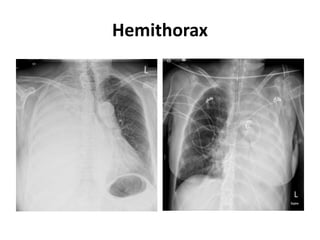

Hemithorax

Mediastinum pushed away from the opacified side

• Pleural effusion

• Large lung mass

• Diaphragmatic hernia

Mediastinum pulled toward the opacified side

• Total lung collapse

• Pneumonectomy

• Pulmonary hypoplasia/agenesis

Mediastinum remains central in position

• Consolidation

• Pleural/chest wall mass

• Combination of pathologies